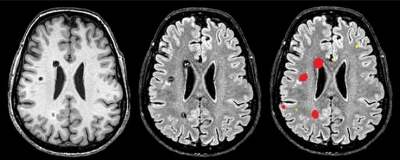

#RICERCA. Angiomatosi Cerebrale Familiare: una nuova terapia con un “vecchio” farmaco per evitare la chirurgia

Un farmaco dal costo di pochi euro ha rivoluzionato la cura di alcune malattie cardiovascolari a partire dagli anni ‘60. Oggi lo stesso principio attivo, il propranololo, potrebbe “cambiare la storia clinica” delle...